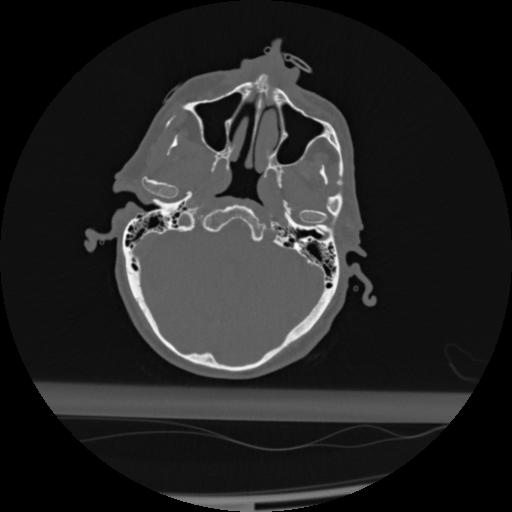

22 ANGIO,CE,Vol,0.5,ANGIO,,